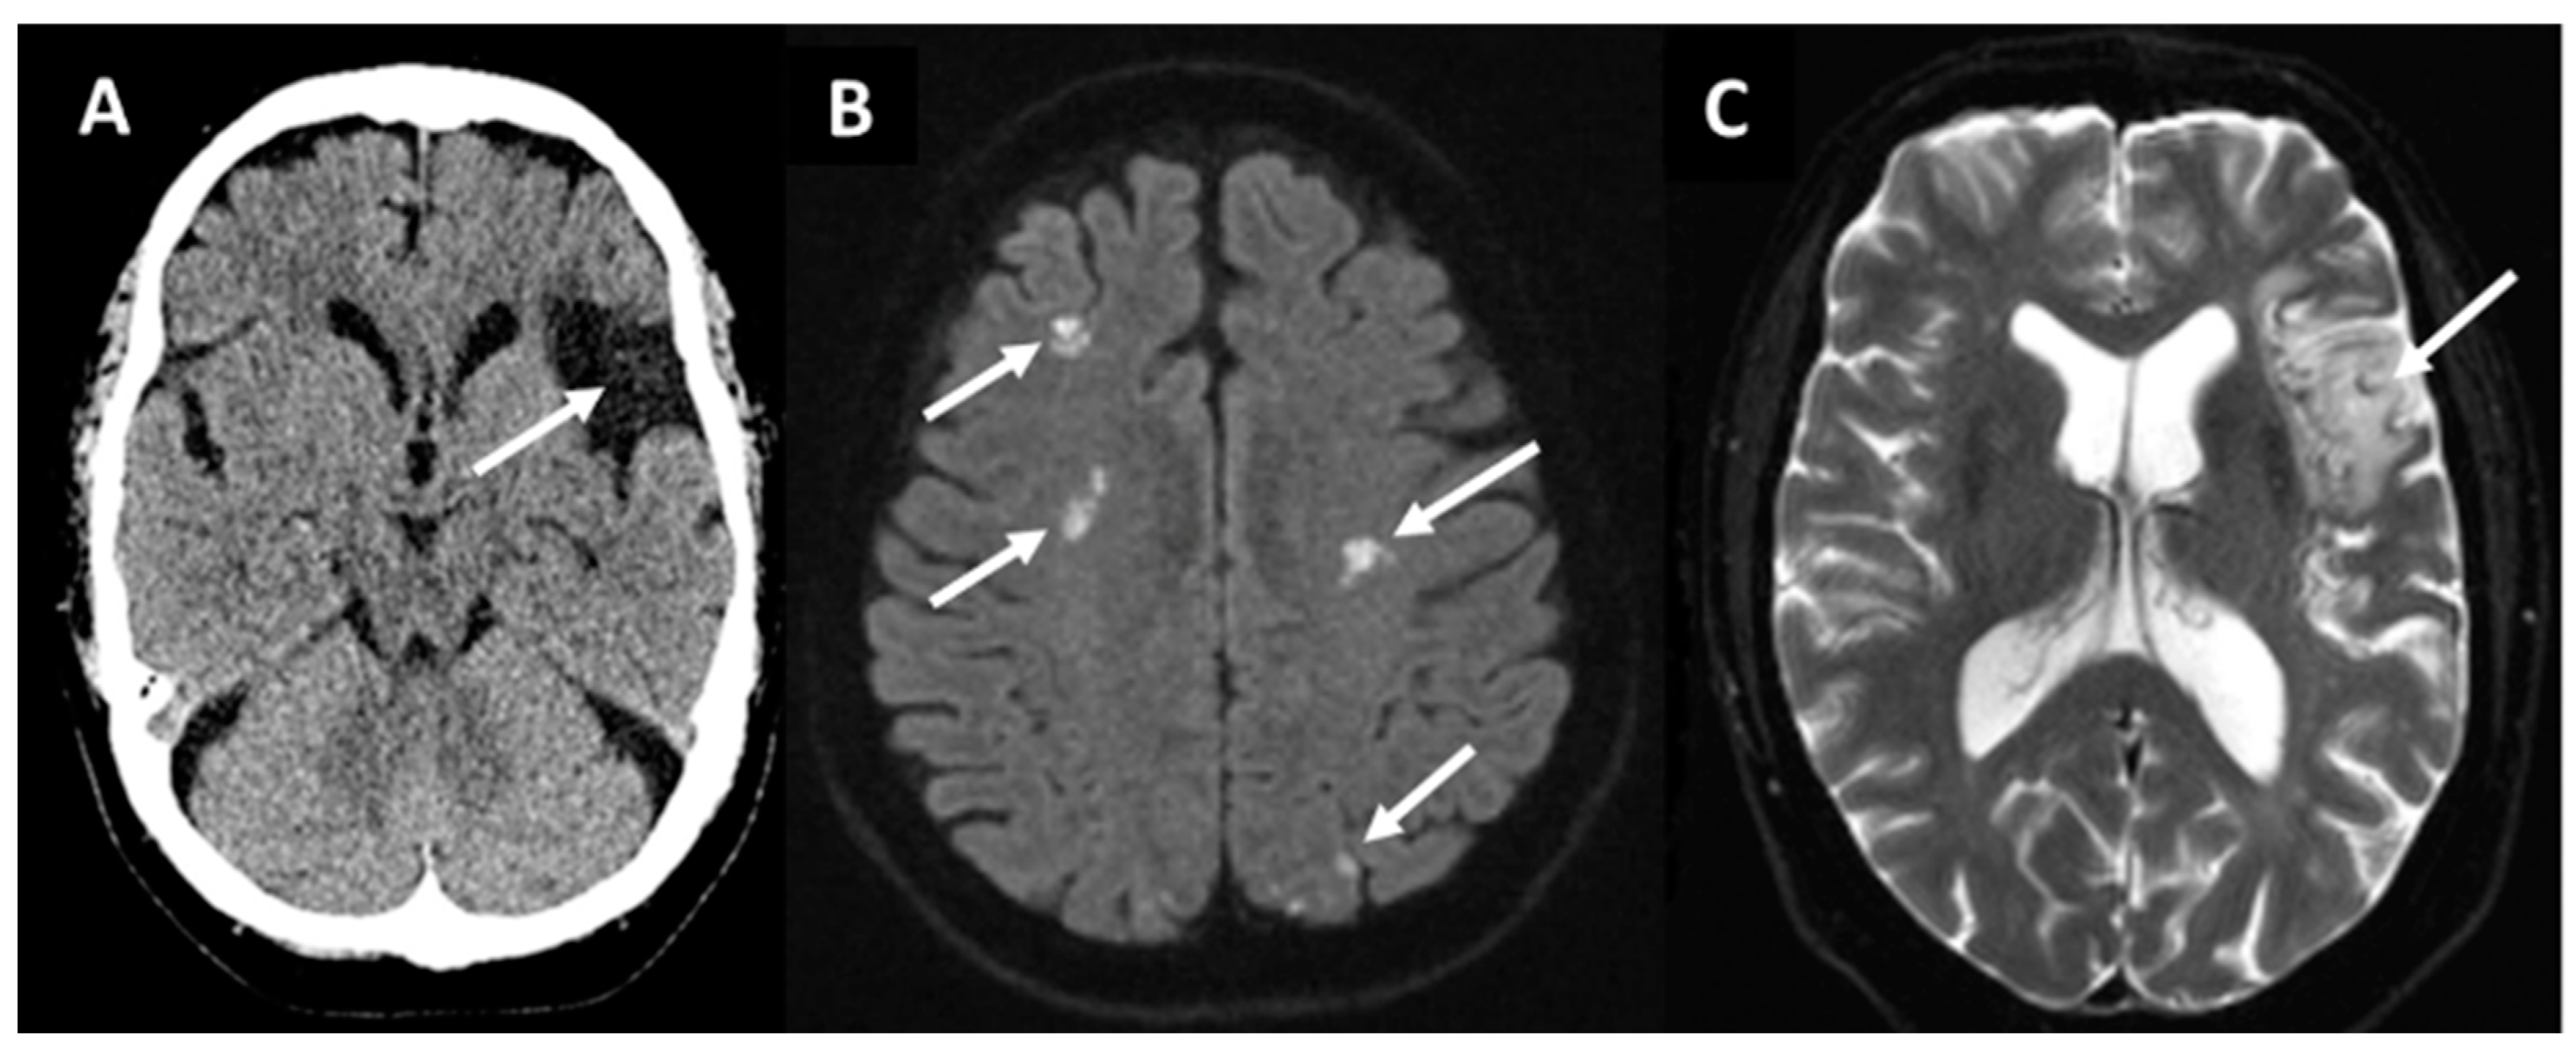

| MRI or NCCT | SVD Prior or acute cortical or cerebellar infarction, multi-territory brain infarction, LVO, CMB, and white matter changes |